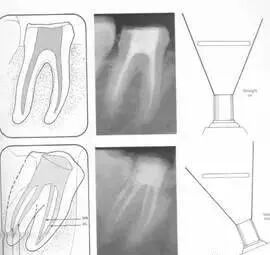

1. 便宜形态

便宜形态是自切端或咬颌面朝向根尖的直线开扩尖锥形态,减少污染物推出根尖孔,方便冲洗、根管充填和侧壁施压。

2. 保持形态

保持形态是根尖狭窄部内 1 — 2mm 的一段距离,由扩大器回转切割而不贴根管壁提拉切割制成,是扩大器的原始形态(近似平行)。在测试主牙胶尖时给测试者有一个牵引抵抗 (tugback) 的感觉。

3. 抵抗形态

抵抗形态是根管预备的根尖形态,它是由扩大器或根管锉尖端 75 度角自然切割而成。其目的是防止根管充填材超出根尖孔,并且使根尖封闭更加严密。

( 1 )直线通路:根管治疗时需要一个直线通路,直线通路能够达到根尖三分之一

测量标准:以允许根管器械直线并直接进入根尖 1/3 且不接触冠方各壁为标准。

( 2 )髓腔其他改变:如髓室顶、继发性牙本质、修复性或增龄性牙本质。见左图。

右图中有继发性牙本质,切削后获得直线通路